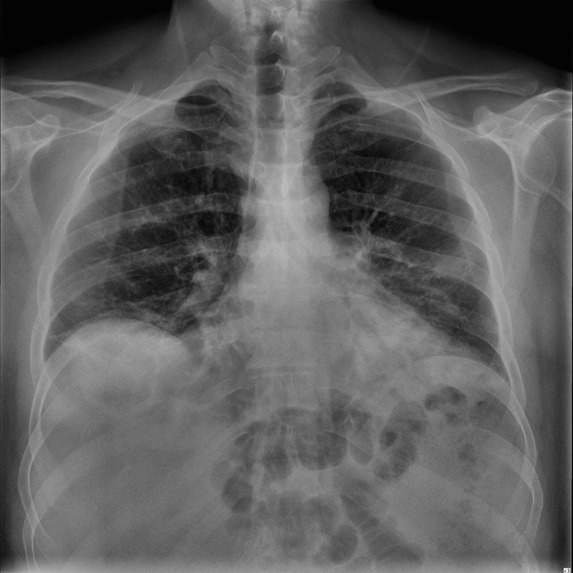

The pandemic has changed our lifestyle and until today it is affecting us, and it is necessary to know every information to keep us and our loved ones safe. With the virus mutating and increased cases of asymptomatic cases now COVID can be being detected using the chest x-rays as it affects the respiratory system first. According to LSU radiologists, these chest x-rays can be used for rapid diagnosis where there are limited testing and delayed results. And as we all know prevention is better than cure with a lot of advice from everyone there is a lot of confusion over the right and spam news. There is a need for expert advice, current news, and rapid diagnosis.

Virtual communication is the new future. In order to help the nurses, patients, and doctors in an effective way, we have created an application that predicts whether a person has COVID or not using Xray inputs from the user and giving advice on the results, The application also gives all the latest information on COVID-19, the preventions following the CDC guidelines, the statistics of COVID-19 cases, and an easy platform to contact doctors to seek advice virtually.